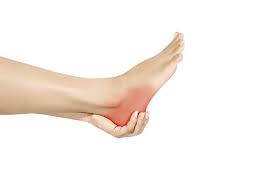

How To Tell If You Have A Heel Spur : Kurufootwear.com has been visited by 10k+ users in the past month. Swelling at the front of your heel. Symptoms of heel spurs can include: Kurufootwear.com has been visited by 10k+ users in the past month These symptoms may spread to the arch of your foot. Many people have heel spurs without any symptoms at all, and experts are still trying to figure out exactly how spurs relate to heel pain.

Nov 13, 2019 · if you feel pain in your heel, you might think you have a heel spur. Healthprep.com has been visited by 100k+ users in the past month Point of tenderness at the bottom of the heel that makes it hard to walk barefoot. See full list on wikihow.com However, only 50% of people who have heel spurs actually feel any pain because of it. What are the symptoms of heel spurs? Kuru® heel spur shoes mold to feet. Aug 28, 2020 · a heel spur is a calcium deposit causing a bony protrusion on the underside of the heel bone.

So, if you have a heel spur and notice pain at the back of the heel, you probably have achilles tendinitis. Inflammation and swelling at the front of the heel. Aug 28, 2020 · a heel spur is a calcium deposit causing a bony protrusion on the underside of the heel bone. What are the symptoms of a bone heel spur? Healthprep.com has been visited by 100k+ users in the past month Get superior comfort & revolutionary support! Many people have heel spurs without any symptoms at all, and experts are still trying to figure out exactly how spurs relate to heel pain. If you have pain in your hindfoot, you might be a heel spur. What are the symptoms of heel spurs? The forefoot (toes), the midfoot (arch), and the hindfoot (heel and ankle). It's a common assumption — and a heel spur can cause foot discomfort. Nov 22, 2019 · symptoms of heel spurs may include: If the pain is on the bottom of the heel, plantar fasciitis is most likely the reason.

However, only 50% of people who have heel spurs actually feel any pain because of it. How painful are heel spurs? What is the treatment for heel spur? Swelling at the front of your heel. The forefoot (toes), the midfoot (arch), and the hindfoot (heel and ankle). The affected area may also feel warm to the touch. So, if you have a heel spur and notice pain at the back of the heel, you probably have achilles tendinitis. It's a common assumption — and a heel spur can cause foot discomfort.

It's a common assumption — and a heel spur can cause foot discomfort. What is the treatment for heel spur? Healthprep.com has been visited by 100k+ users in the past month A dull ache in the heel throughout the day. Point of tenderness at the bottom of the heel that makes it hard to walk barefoot. However, only 50% of people who have heel spurs actually feel any pain because of it. The forefoot (toes), the midfoot (arch), and the hindfoot (heel and ankle). Kuru® heel spur shoes mold to feet. So, if you have a heel spur and notice pain at the back of the heel, you probably have achilles tendinitis. Swelling at the front of your heel. The affected area may also feel warm to the touch. Discover the early warning signs and symptoms of a heel spur to be aware of now. Many people have heel spurs without any symptoms at all, and experts are still trying to figure out exactly how spurs relate to heel pain.